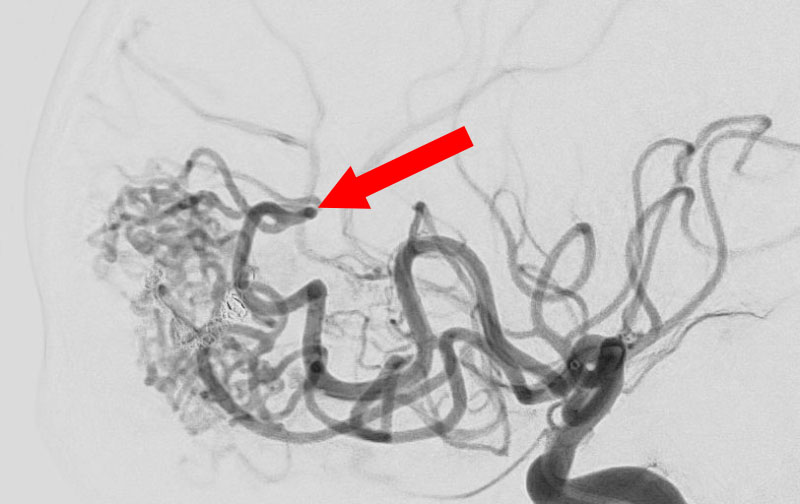

'25年10月

脳動静脈奇形

60代

大阪府の病院

No.1583 手術前

No.1583 手術中

No.1583 手術後